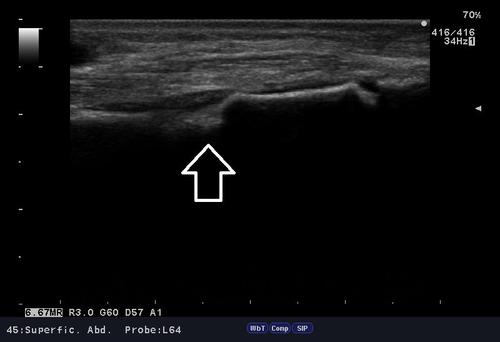

自転車で転倒した際、左手を突いた時に、手首を痛めたと御来院。

問診、視診、触診、そしてエコー検査。

結果「橈骨遠位端部骨折」の部位を確認。

腫れ具合から骨折の有無はある程度予想できますが、エコー検査は骨折の箇所を的確にその場で確認でき、骨癒合を促進させるマイオパルス(MYO PULSE)という治療器で、治療を行えるので強い味方です。